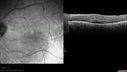

SPECTRALIS-SD-OCT SCAN: The OCT scan shows macular edema in both eyes with a serous macular detachment in the left eye. There are intraretinal cysts and retinal atrophy in the far periphery. The OCT scan does show atrophy of the outer retina.